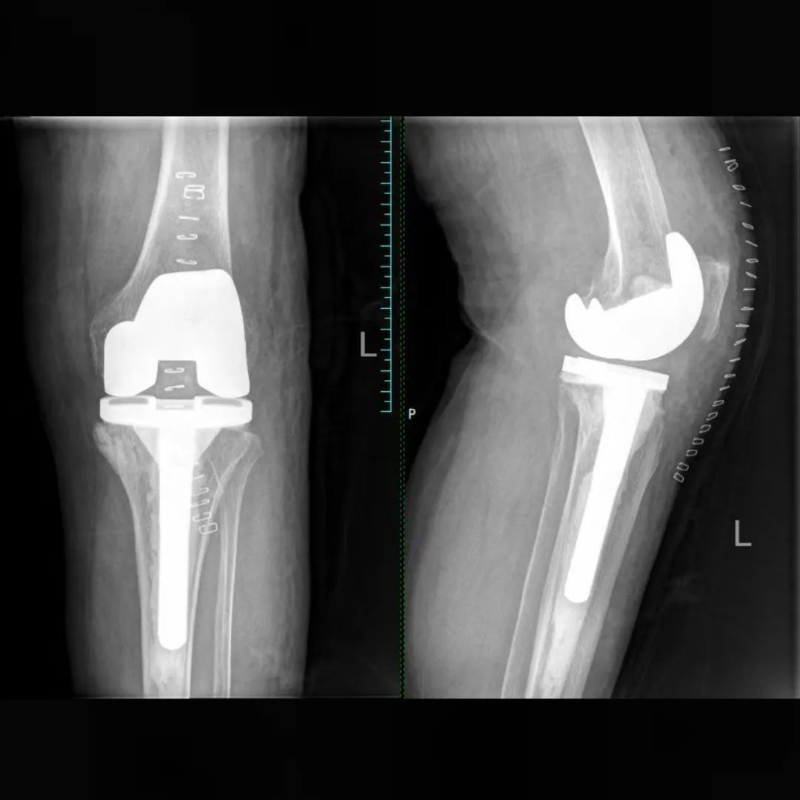

70多歲的葉阿姨,被膝關(guān)節(jié)骨關(guān)節(jié)炎困擾多年,就診時雙側(cè)膝關(guān)節(jié)已明顯畸形,無法正常行走,病變嚴(yán)重到均需要行人工膝關(guān)節(jié)置換,而癥狀更重的一側(cè),CT顯示脛骨平臺下方有一巨大骨囊腫,所以對于平臺假體的安放成了棘手的問題,通過AI術(shù)前規(guī)劃很好的解決了這個問題,規(guī)劃能明確截骨的厚度,獲知囊腫的范圍從而提前做好處理預(yù)案,進(jìn)而確定選擇合適的假體,術(shù)中基本按規(guī)劃和預(yù)案進(jìn)行,假體安放順利,安放牢固。患者術(shù)后第二天就能下床活動,出院時對手術(shù)效果很是滿意,已經(jīng)預(yù)約三個月后再做另一側(cè)關(guān)節(jié)的手術(shù)。

文章配圖

△術(shù)前

△術(shù)后